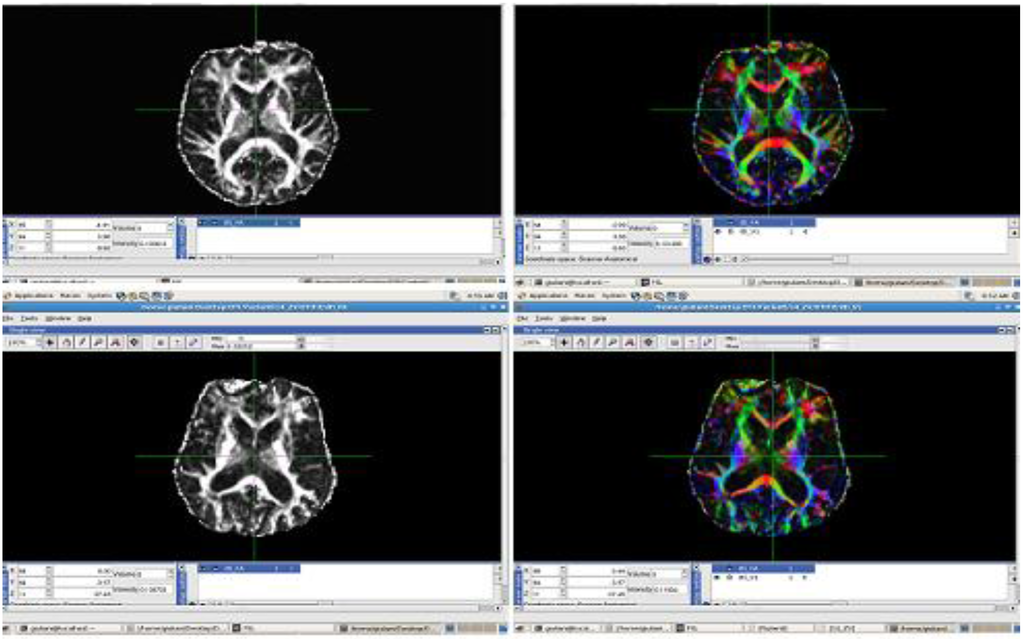

The processed GM and FA images were derived from a dataset composed by a group of 17 patients affected by Alzheimer’s disease and a control group of 11 unities. MRI images were acquired using a 3 Tesla Siemens Impact scanner at the Neuroradiology Unit of the Ospedale Maggiore Borgo Trento, Verona, Italy (2008) with a standard head coil. Axial diffusion tensor images (DTI) were acquired with diffusion encoding gradients applied in thirty noncollinear directions and a b-factor of 1000 s/mm2, plus five images without diffusion weighting. The following parameters were used: TR = 5000 ms, TE = 118 ms, number of slices = 23, slice thickness = 5 mm, slice gap = 1 mm, acquisition matrix = 128 × 128, FOV = 220 mm, the scan duration was 3 min. FA and directional maps for two subjects are shown in Figure 9, the images were realized by using the Software Tools FSL 4.0 (Figure 9 and Figure 10) (Functional Software Library of the FMRIB Centre, Oxford Centre for Functional Magnetic Resonance Imaging of the Brain-Oxford University) [18,19].

Figure 9. FA and directional Maps derived by the Software Tools FSL.

Algorithms 05 00636 g009